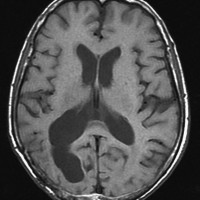

70歳女性の右後頭葉退形成性星細胞腫に対して,摘出術と54グレイ27分割の局所放射線治療をしました。右後頭葉に腫瘍摘出腔があって腫瘍再発はないのですが,治療一年後くらいから脳梁の脳室側にFLAIRで高信号の領域が広がってきました。特に星細胞系腫瘍の場合に,局所浸潤再発とまがうような所見となることもあります。ここにあげた例は典型的なもので,脳梁膨大部から膝部に至るまで脳梁内側部の白質変性が明瞭にとらえられます。